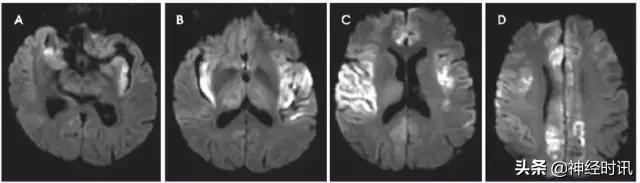

图4 一例72岁男性,精神状态改变,右下肢局灶性运动性癫痫持续状态,同时存在发热伴分泌性咳嗽。该患者最初被诊断为双侧ACA和MCA脑梗死。最后患者被诊断为HSV脑炎,MRI显示双侧颞叶、额叶、岛叶、扣带回和丘脑非对称性多灶性弥散受限(A-D,DWI)、T2/FLAIR高信号(图像未提供)。

图5 一例51岁女性,表现为意识不清,言语含糊,近事遗忘。发病后4天DWI显示双侧海马点状弥散受限(A&B:DWI;C&D:ADC)。随访MRI显示病灶完全缓解(图像未提供)。